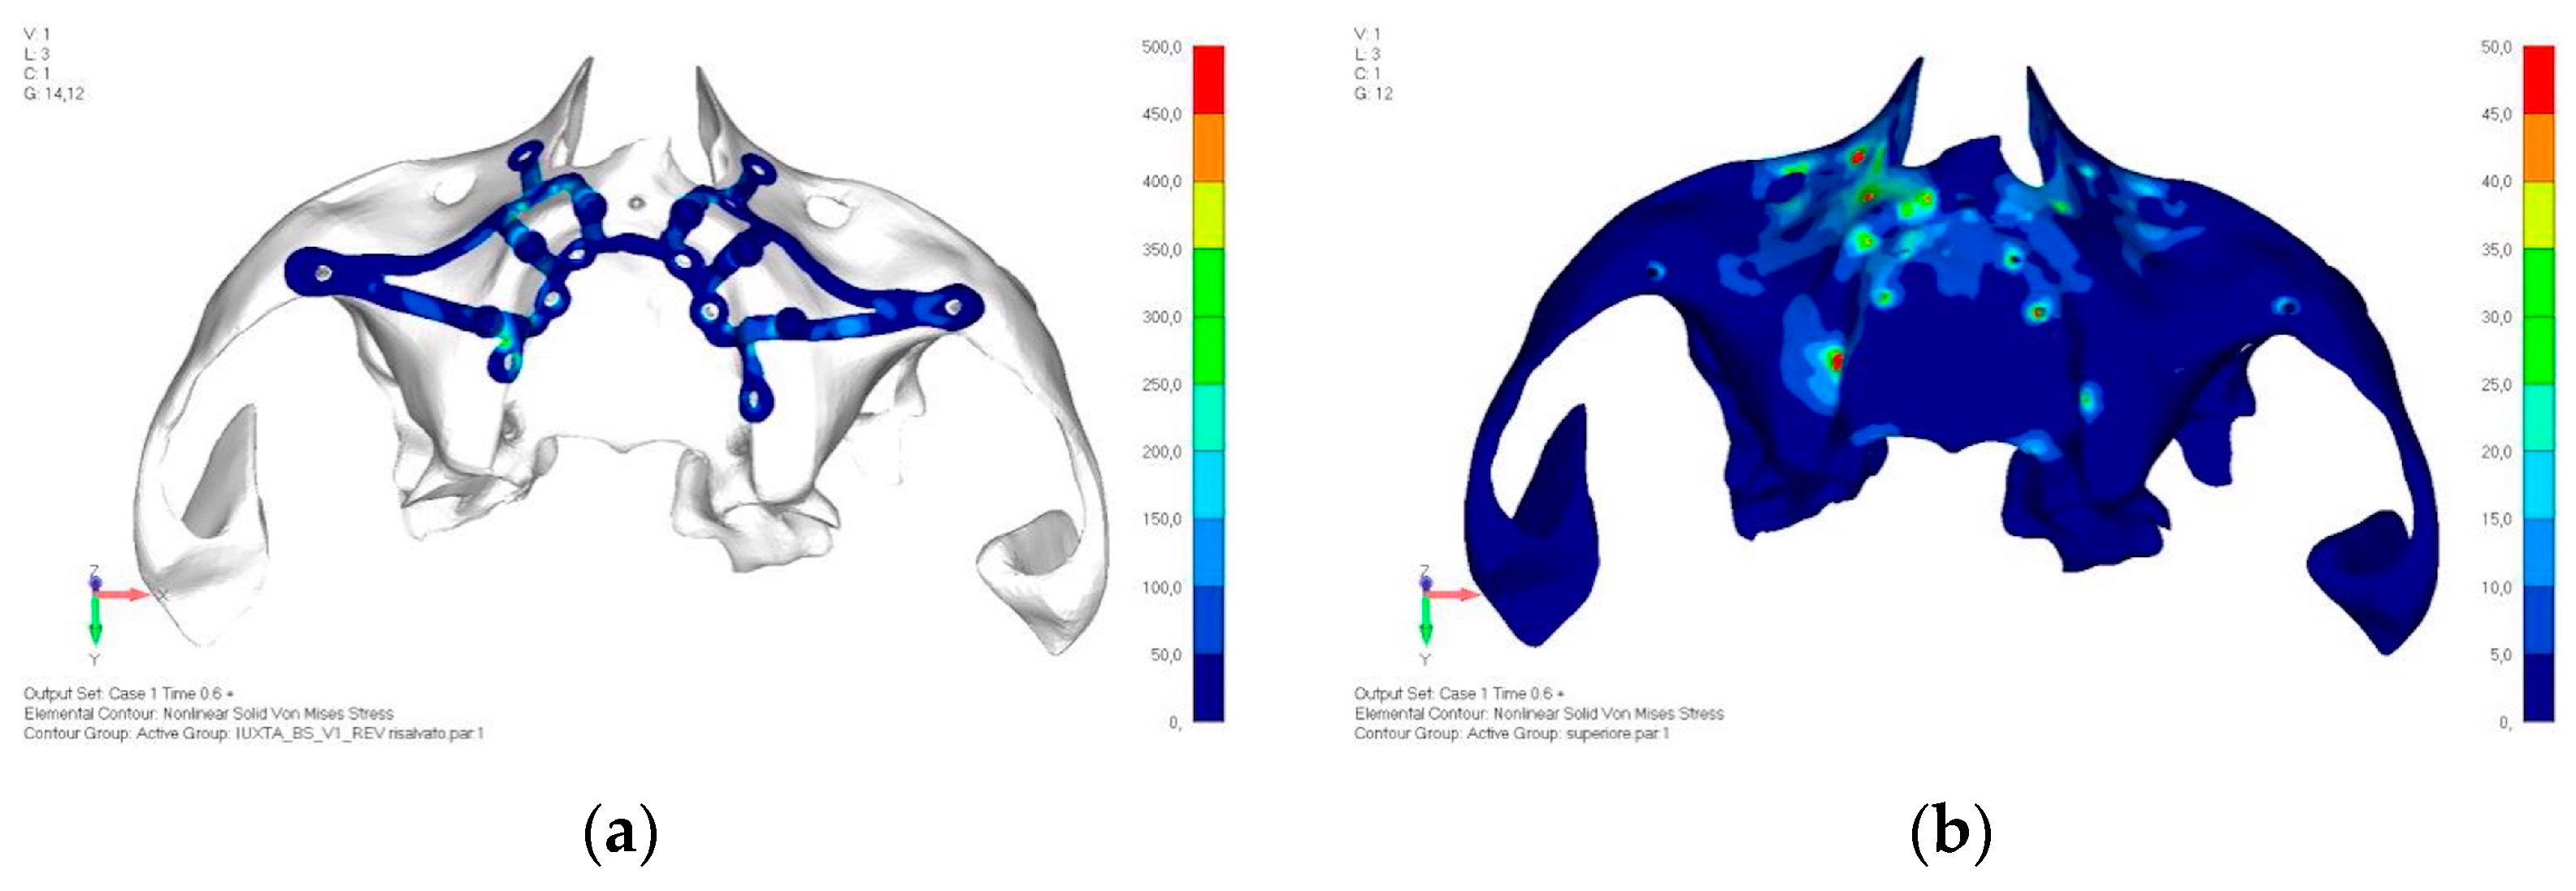

- Model V1. Added posterior screws, reducing stress on anterior parts and achieving more balanced distribution. The addition of the posterior screw has certainly alleviated the load on the palatal screw, which was excessively stressed in the previous model (Figure 8). The screw now experiencing the most stress is the posterior screw: compared to the previous case, only part of the hole shows a stress exceeding 50 MPa, and the area affected by this stress is therefore much more contained (Figure 9a,b).